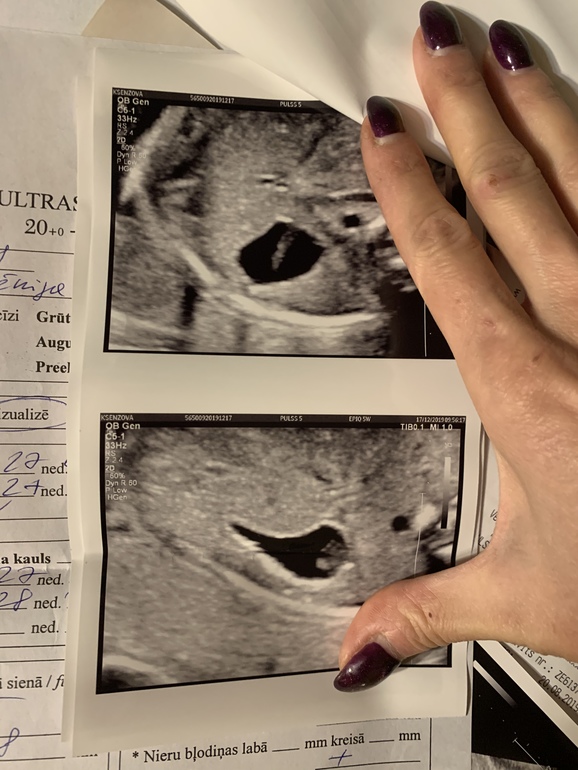

Вопросы про УЗИ, обследования и анализы: что, где, как, когда?Была на узи внеплановом. До этого все узи пройдены и все хорошо было. Предпоследнее в 20 недель. Сейчас срок 27-я неделя. На узи у малыша в желудке увидели какое то образование. Она удивилась почему в 20 недель мне ничего не сказали. Что это она не знает, но этого там быть не должно. Может опухоль, может полип или киста... не знает она. Сказала отдайте узи врачу пусть он решает, что с вами делать. Так жутко стало. Желудок чёрного цвета - это жидкость, а у нас, как ткань какая то полосой. На фото видно. Девочки, может у кого было что то похожее напишите пожалуйста что это может быть и стоит ли переживать.